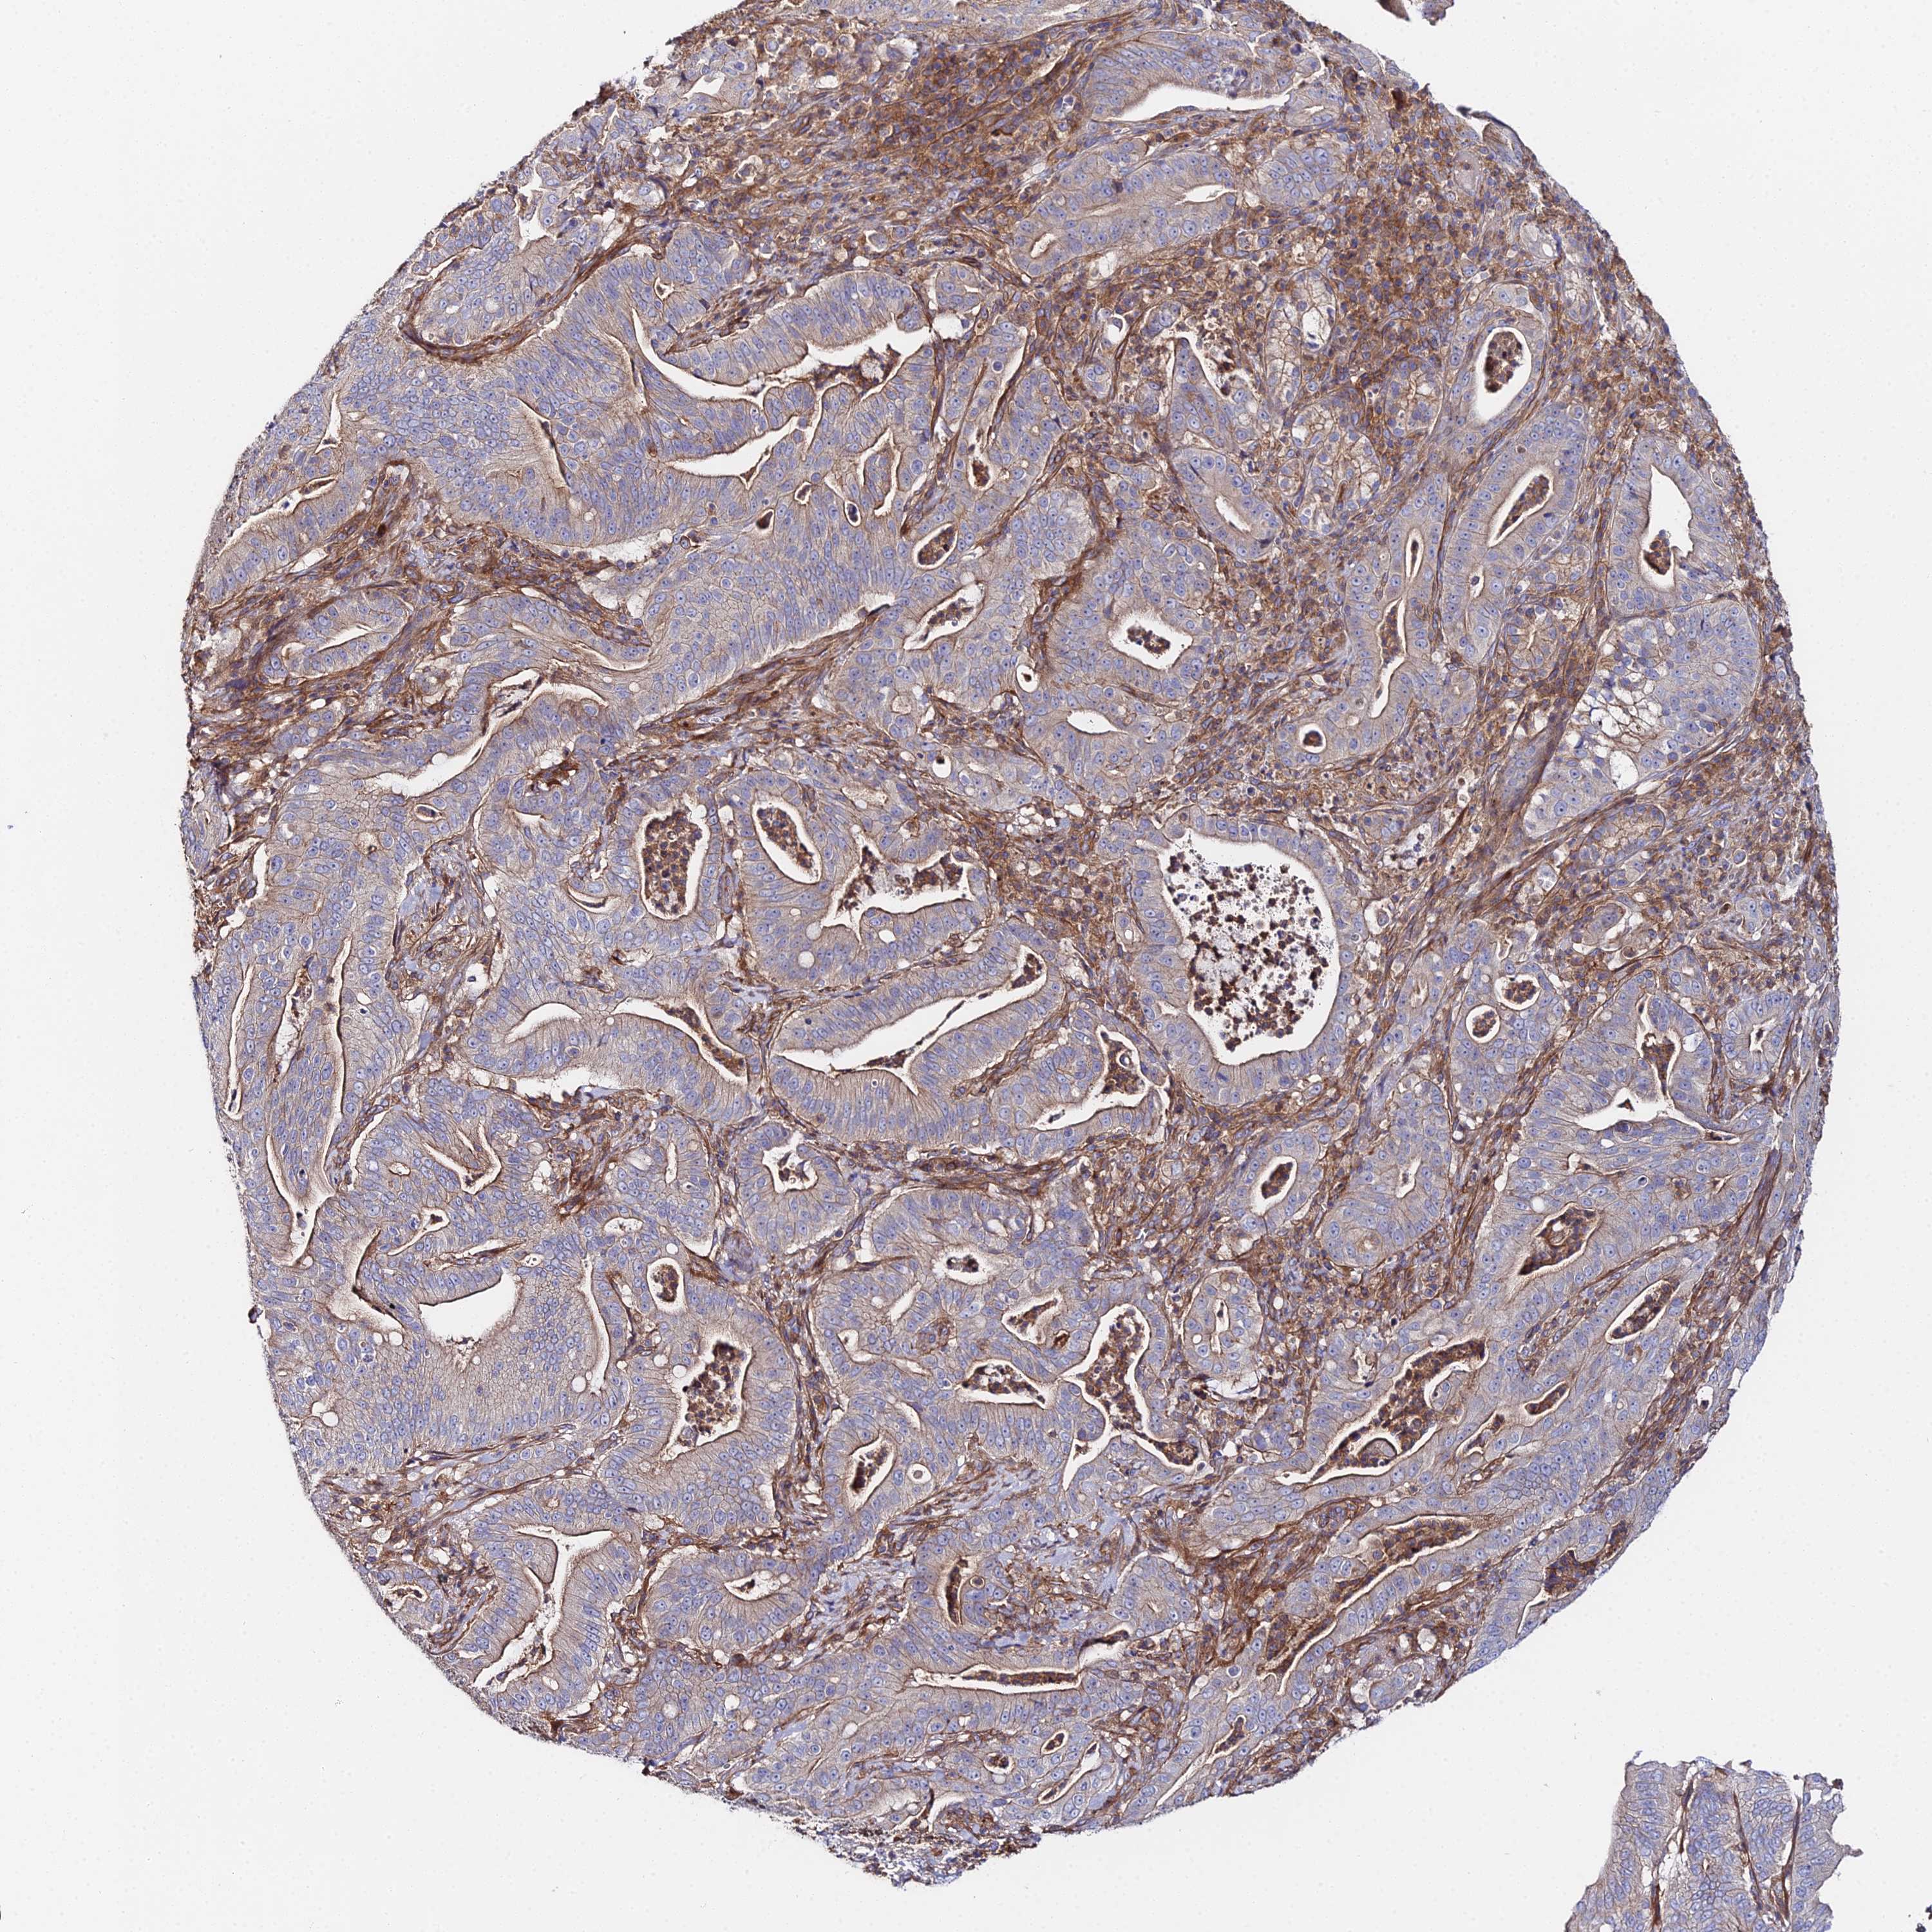

PANCREATIC CANCER - Protein expressioni

A mouse-over function shows sample information and annotation data. Click on an image to view it in a full screen mode. Samples can be filtered based on level of antibody staining by selecting one or several of the following categories: high, medium, low and not detected. The assay and annotation is described here.

Note that samples used for immunohistochemistry by the Human Protein Atlas do not correspond to samples in the TCGA dataset.

Antibody stainingi

Antibody staining in the annotated cell types in the current human tissue is reported as not detected, low, medium, or high, based on conventional immunohistochemistry profiling in selected tissues. This score is based on the combination of the staining intensity and fraction of stained cells.

Each image is clickable and will lead to virtual microscopy that enables deeper exploration of all samples and also displays staining intensity scores, fraction scores and subcellular localization as well as patient and tissue information for each sample.

Antibody HPA043651

Antibody CAB032623

Adenocarcinoma, NOS